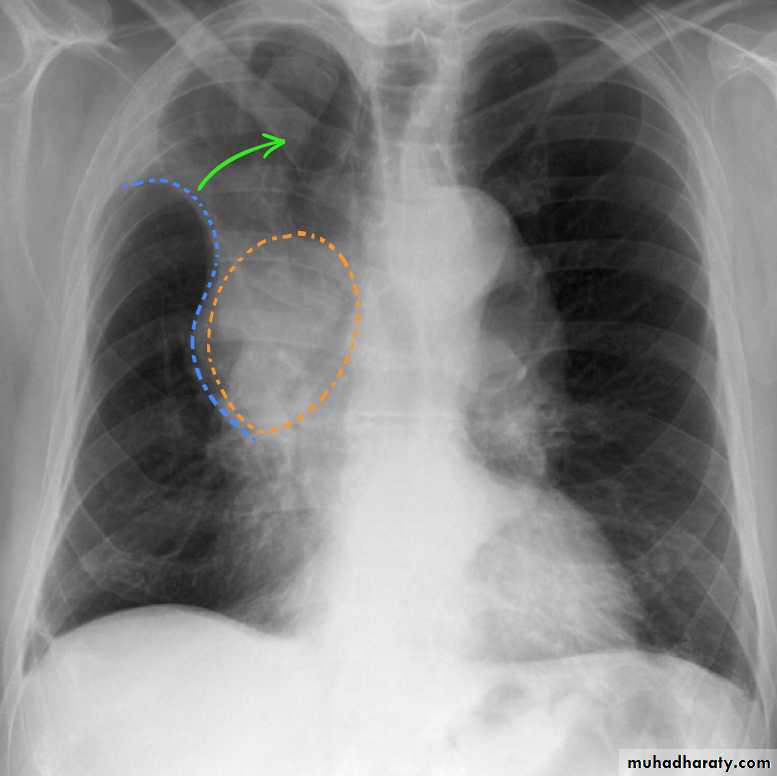

Mitral valve diseaseCXR of adult male , PA view shows: Enlargement of the cardiac shadow (cardiomegaly), Enlargement of left atrium Double density sign: the right side of the enlarged left atrium pushes into the adjacent lung and creates an addition contour superimposed over the right heart.

Mitral valve disease (double density RT cardiac border)CXR of adult , PA view shows: Cardiomegally Double density sign of right cardiac border Enlargement of left atrium, permenant left atrial appendage and relaced mitral valve (prosthesis)